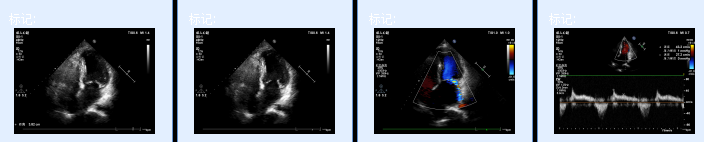

超声评估

超声心动图显示:患者左房大,室间隔增厚,二尖瓣轻中度反流,左室舒张功能障碍。左房内径51mm,LVDd=40mm,LVDs=21mm,LVEF=45%